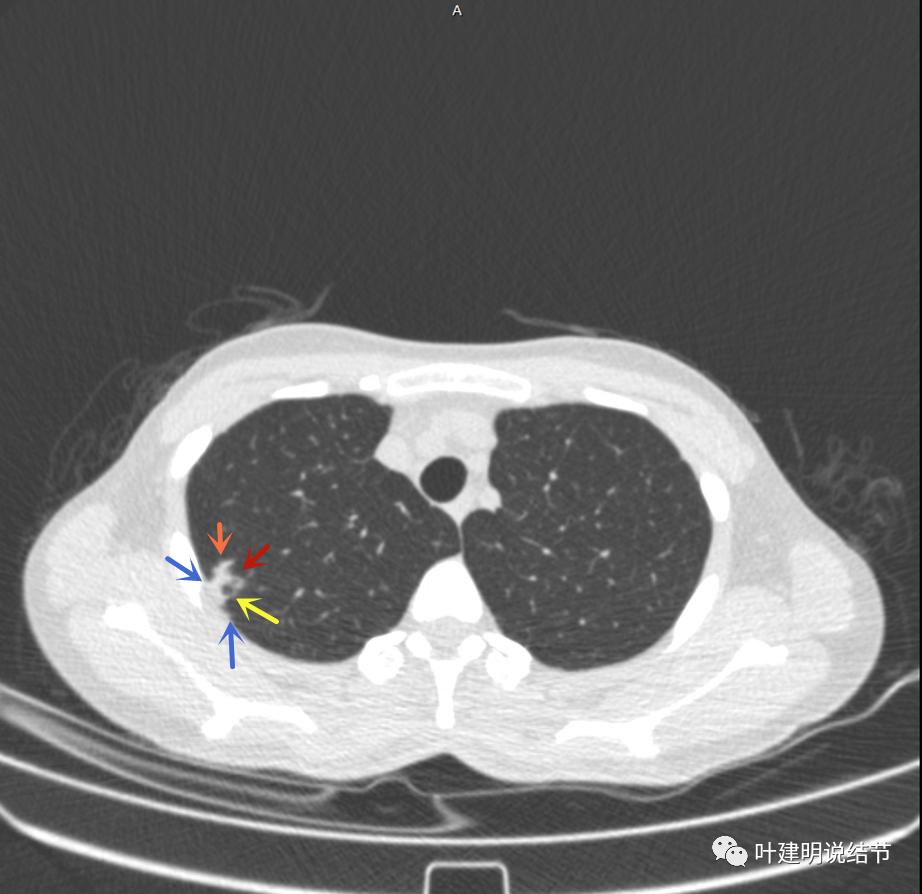

上面是她提供的病史资料,其中最重要的是PPD强阳性!其他主要看影像,我们先来看她2020年7月份的平扫片子(由于片子较多,详细展示是为了同道分析,我在影像特征描述上将只选取部分加以说明):

右肺尖偏实性结节(粉色箭头),邻近胸胸膜明显增厚不平,且广基附在胸壁上(蓝色箭头)

有卫星病灶(绿色箭头)

胸壁侧病灶较厚,模糊(蓝色箭头),仍见卫星灶(绿色箭头)

主病灶出现,粉色箭头示病灶密度较高,边上有磨玻璃影,甚淡(砖色箭头)

病灶有空洞(黄色箭头),主病灶边上见条索状高密度影(细红色箭头),邻近胸膜有粘连(蓝色箭头)

邻近胸膜明显增厚,且广基底,主病灶前方有小片磨玻璃影

主病灶与胸膜间基本相连,模糊清(蓝色箭头),主病灶壁厚薄欠均,边上有高密度条索状(桔色箭头)

主病灶不见了的层面,仍有边上高密度条索状的影像,邻近胸膜仍有异常(蓝色箭头)

影像初印象:右上病灶散在,不致密,密度偏高,磨玻璃影不是平时典型恶性的磨玻璃瘤肺边界清楚或含毛刺征的征象,更符合炎性病变,且邻近胸膜广基的异常增厚。